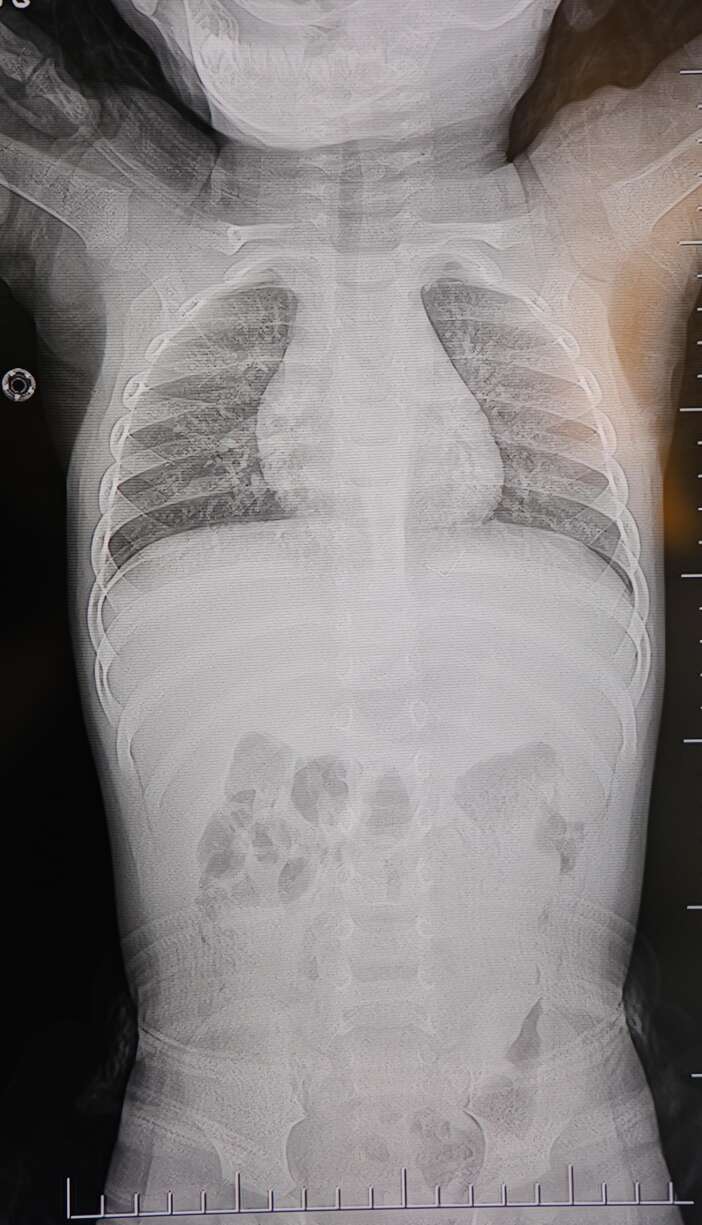

Kahramanmaraş'ta sırt üstü yatmak istemeyen ve yatırıldığında ağlayan bebeğin sırtından akciğer zarına doğru ilerleyen 2 santimetrelik zımba teli çıktı.

Aile, bebekleri için son olarak HG Hospital'e başvurdu. HG Hospital Beyin ve Sinir Cerrahisi Uzmanı Prof. Dr. İdris Altun tarafından yapılan tetkiklerde, yabancı cismin cilt altında, omurilik kanalına yakın bir bölgede olduğu ve akciğer zarına doğru ilerlediği belirlendi.

Hasta, genel anesteziye alınmadan, lokal anestezi ve sedasyon eşliğinde ameliyata alındı. Yapılan müdahalede yabancı cisim tamamen çıkarıldı. Çıkarılan cismin, ince zımba teline benzer metal bir tel olduğu ve yaklaşık 2 santimetre uzunluğunda bulunduğu tespit edildi. Hasta, aynı gün taburcu edildi.

Konuya ilişkin açıklama yapan Prof. Dr. İdris Altun, "Sırtında yabancı bir cisim olduğu söylenmiş ancak çıkarılamayacağı ve 8 yaşına kadar beklenmesi gerektiği ifade edilmişti. Bize başvurduğunda yaptığımız tetkiklerde, cilt altında, omurilik kanalına çok yakın ve akciğer zarına doğru ilerleyen bir yabancı cisim tespit ettik. Hastamızı tamamen uyutmadan, lokal anestezi ve sedasyon eşliğinde müdahale ederek lezyonu tamamen çıkardık. Çıkardığımız cismin ince zımba teline benzer, yaklaşık 2 santimetre uzunluğunda metal bir tel olduğunu gördük. Bu yabancı cisim alınmasaydı, bölgede enfeksiyon gelişebilirdi. Enfeksiyon sonucu omurilik kanalında ciddi hasarlar oluşabilir, çocuk büyüdükçe cismin hareket etmesine bağlı olarak omurilikte zedelenmeler meydana gelebilirdi. Ayrıca yana doğru ilerleyerek akciğer zarına ve akciğere batma riski vardı. Bu da enfeksiyona ve ilerleyen süreçte tümörle karışabilecek tablolara neden olabilirdi. Şu an hastamız gayet sağlıklı. Gerekli kontrolleri yaptık ve aynı gün taburcu ettik" dedi.